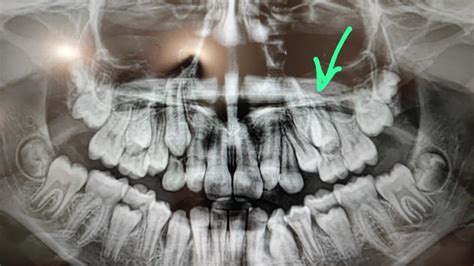

El odontopediatra es el profesional encargado de explorar y tratar al paciente infantil, detectando posibles anomalías en la posición de los maxilares o dientes.

- Detección Temprana: Identifica anomalías en la posición de los maxilares o dientes.

Una de las principales diferencias entre la odontología general y la odontopediatría es la presencia de los dientes temporales o de leche en los niños.

Sería conveniente que la primera revisión por un ortodoncista se realizara alrededor de los 7 u 8 años. En esas edad, el grupo de dientes incisivos superiores e inferiores ya han erupcionado. Sabemos que los dientes temporales son muy importantes para que el niño se desarrolle correctamente.